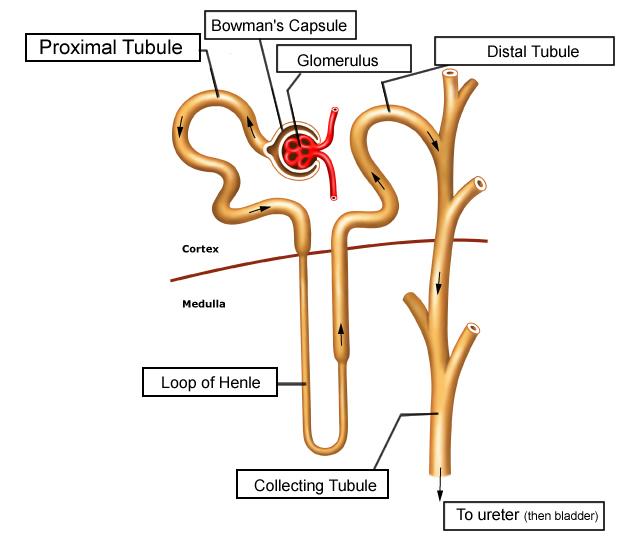

Collecting duct

Descending/Ascending loop (of nephron)

Distal (convoluted) tubule

Glomerular capsule (=Bowman's capsule)

Glomerulus (=glomerular capillaries)

Juxtaglomerular apparatus

Nephron

Peritubular capillaries

Proximal (convoluted) tubule

Renal corpuscle